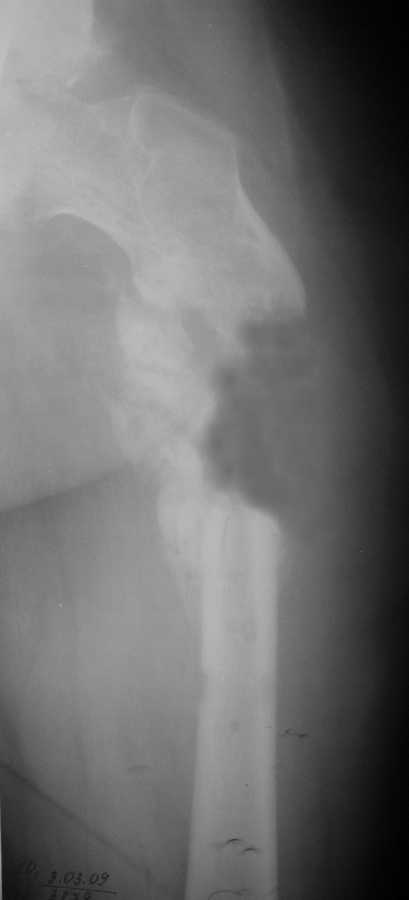

Уважаемые коллеги, у пациента 26 лет имеется дефект в\з бедренной кости образовавшийся в результате СНЭ по поводу травматического остеомиелита

Также имеется травматическая деформация таза с трансвертлужным переломом на стороне дефекта.

Планируется замещение дефекта транспортом кости.

Хотелось бы услышать ваши советы по поводу оптимальной компоновки АВФ (стержневой, спице-стержневой), есть ли необходимость в дополнительной фиксации за кости таза?